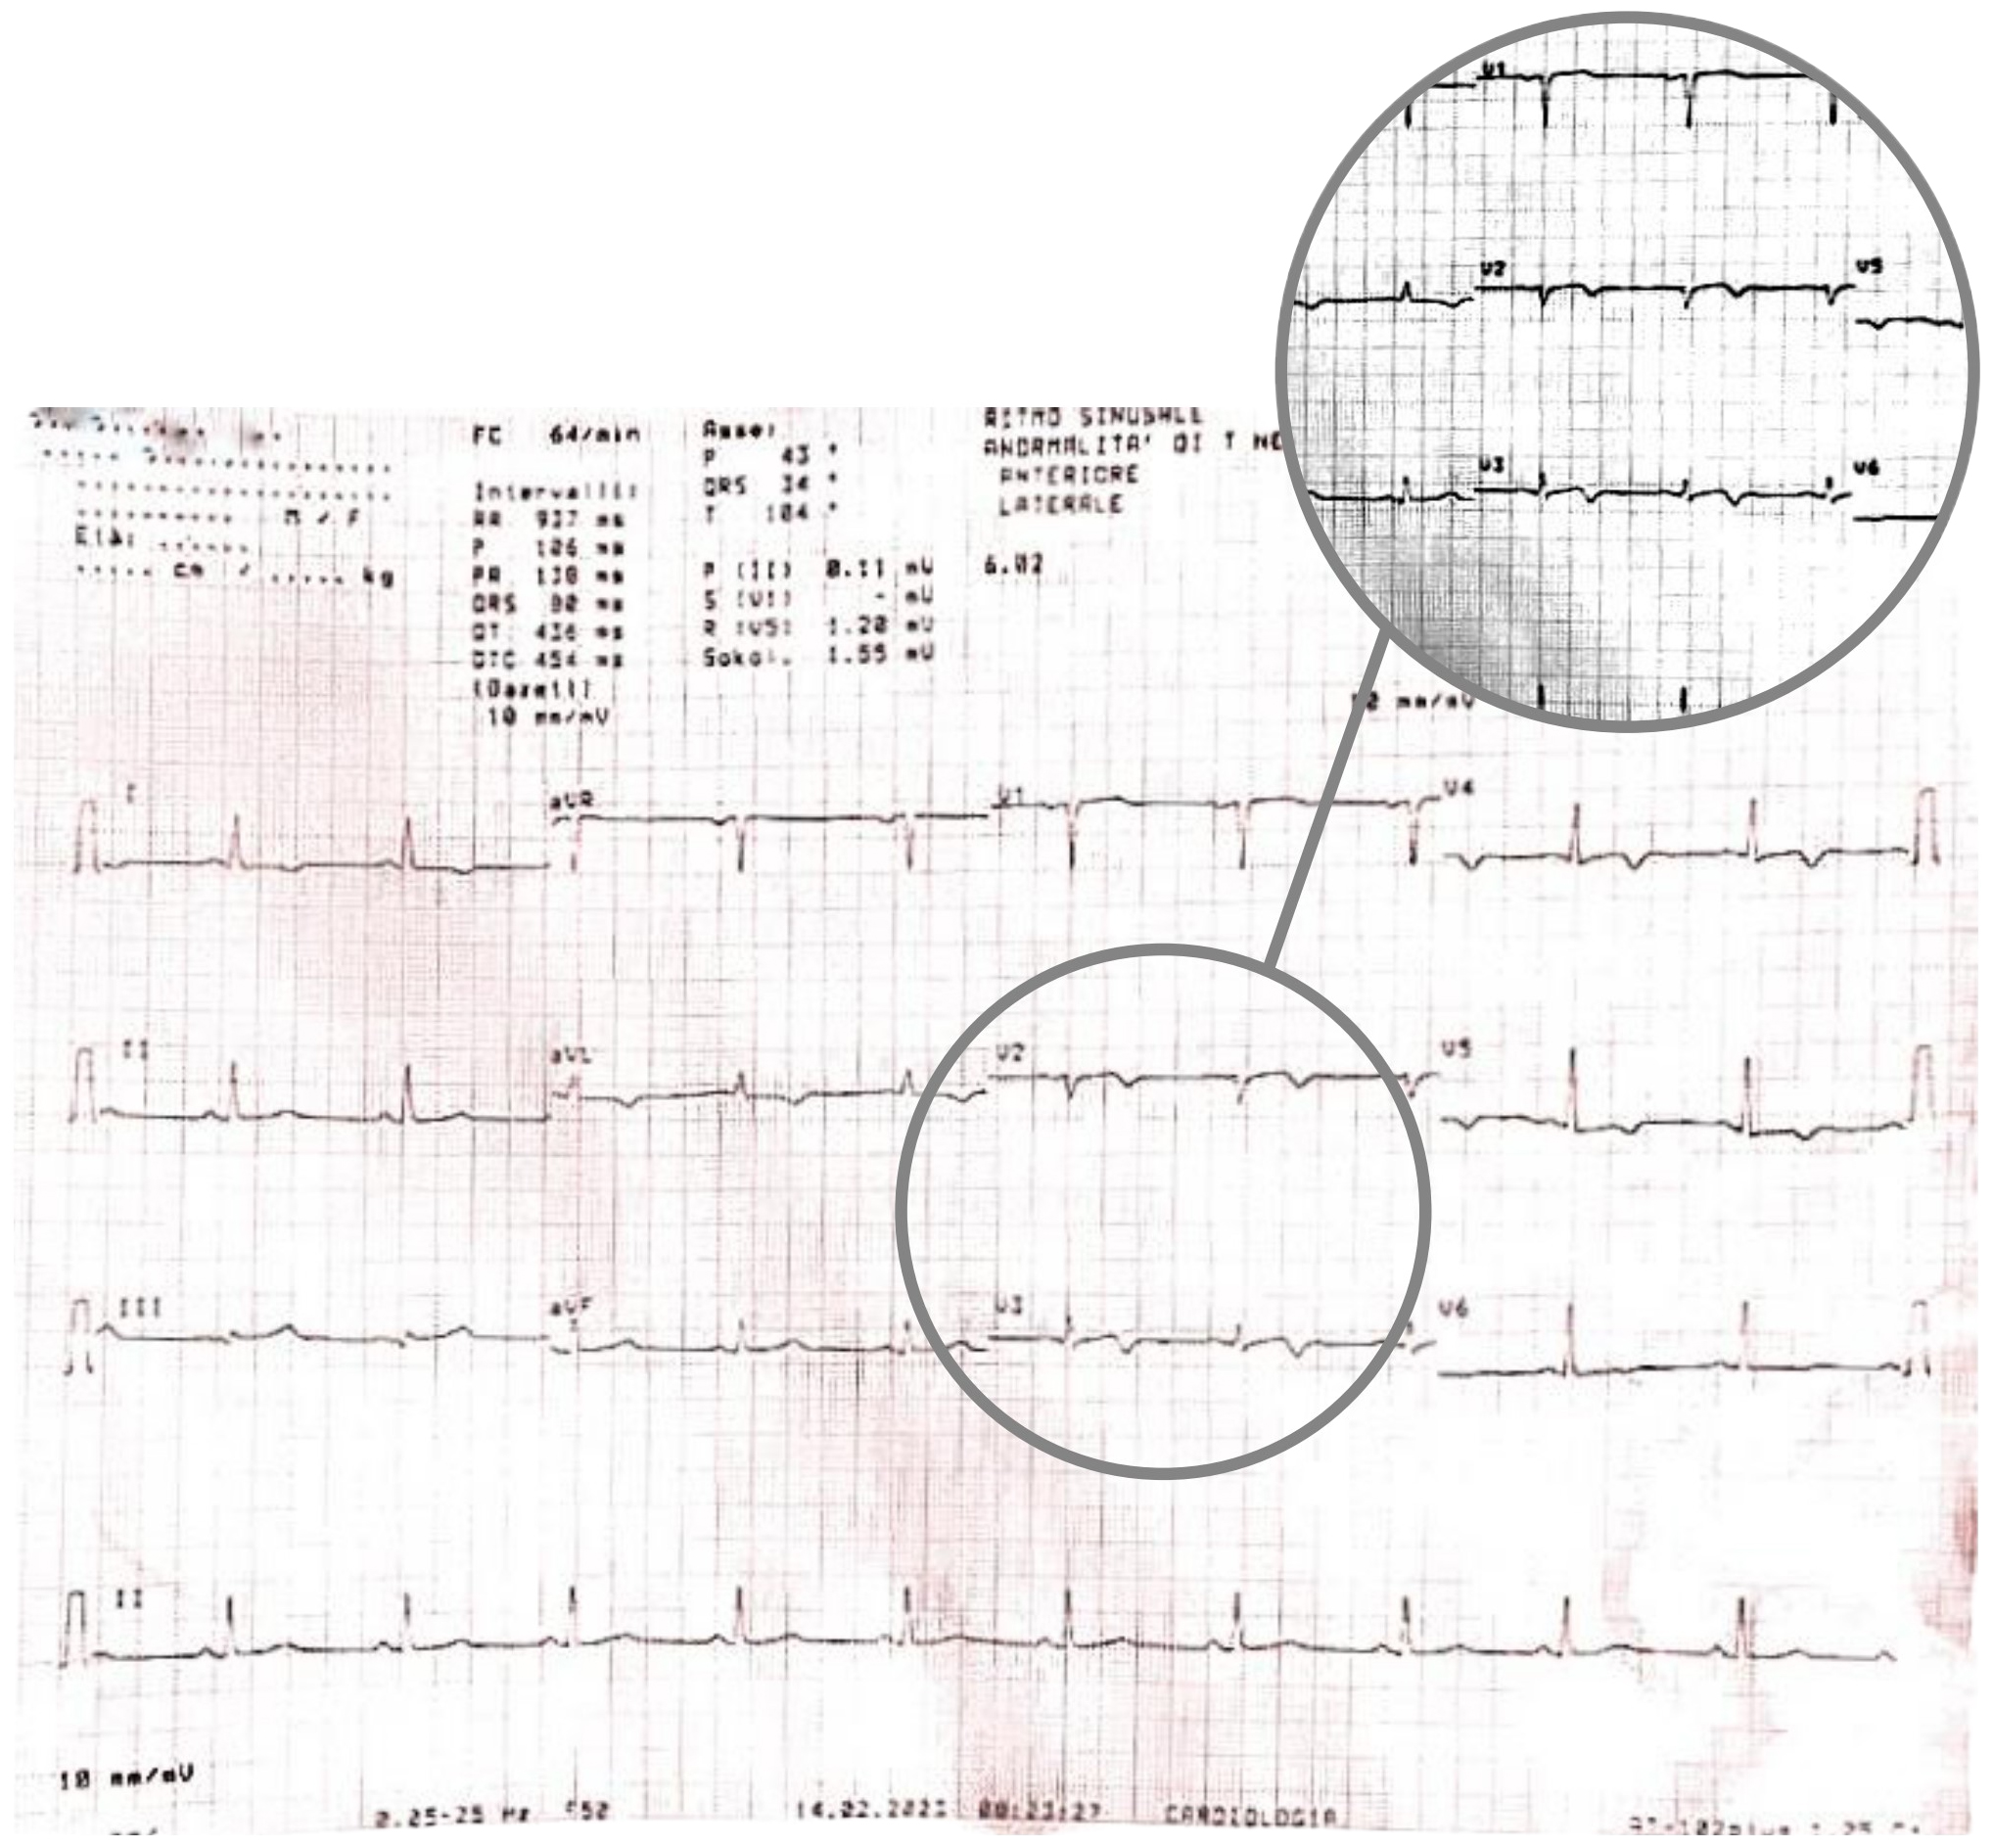

A few minutes later, the patient experienced a further episode of chest pain, which occurred at rest, but was of greater intensity and duration, and had no clear triggering factors, another 12-lead ECG was performed and showed some differences compared to previous recordings: symmetrically inverted T waves were evident in leads V2 and V3, this time resembling a type B Wellens pattern (Fig. 5 — ECG). As discussed above, these ECG patterns, in a patient admitted for chest pain with slightly elevated serum cardiac markers and negative 3-hour hs-troponin T delta, should raise suspicion of Wellens Syndrome, which is highly specific for critical stenosis of the LAD.

Fig. 5.

Fig. 5.ECG showing symmetrically inverted T waves in leads V2 and V3, resembling a type B Wellens pattern. ECG, electrocardiogram.